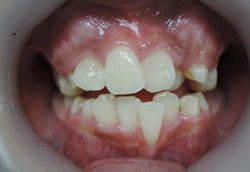

歯並びの悪い症例

口腔機能を順調に発育発達させる為には早期治療が効力を発揮します。

多数の治療法がありますが、当院ではブラケットという矯正装置を歯に装着する事で、上下顎骨の大きさと、咬み合わせの高さを改善していきます。

前歯がクロスしていて将来、口腔機能に悪影響を及ぼす事となります。

①前歯のクロスを改善するためには咬み合わせを高くする必要があります。

当矯正歯科医院では上顎の乳臼歯にレジンを盛る事で、クロスした前歯の被蓋(前歯の咬み合わせ)を改善していきます。

前歯のクロスが改善されて治療しやすくなっています。

その後、ブラケット装着を使用して上顎骨の拡大を始めます。